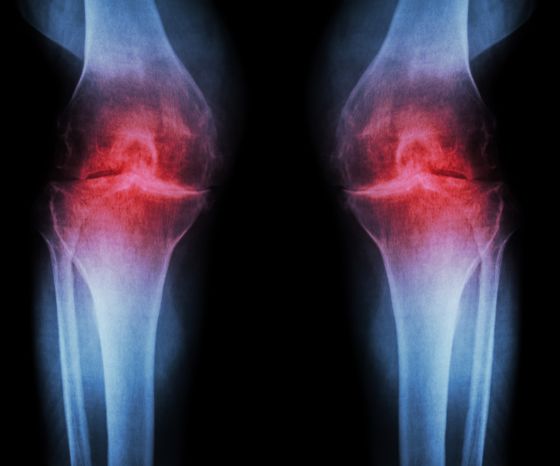

Класическа характеристика на остеоартрита на коляното са хистологичните промени в качеството и дебелината на ставния хрущял. Намаляването на ставния хрущял води до хипертрофия на субхондралната кост и образуване на остеофити по ръбовете на ставните повърхности. Друга последица е хроничното възпаление на синовиалната тъкан. Всички тези промени водят до неравномерни ставни повърхности, костно уголемяване, евентуално удебеляване на ставната капсула и в крайна сметка до хидропс. Полученото в резултат на това намаляване на ставното пространство се вижда на рентгенографски снимки, поради което се говори и за "рентгенологичен остеоартрит".

Най-често използваната система за класификация на рентгенологичния остеоартрит е скалата на Kellgren & Lawrence(Kohn et al. 2016):

- Степен 0: няма рентгенографски признаци на ОА

- Степен 1: съмнително стесняване на ставното пространство и възможно остеофитно устие

- Степен 2: определени остеофити и възможно стесняване на ставното пространство на предно-задна рентгенография с тежест

- Степен 3: множество остеофити, определено стеснение на ставното пространство, склероза, възможна костна деформация

- Степен 4: големи остеофити, изразено стеснение на ставното пространство, тежка склероза и определена костна деформация.